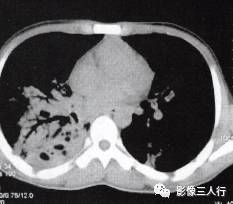

原发性肺淋巴瘤在影像上可呈现肺实质内或肺门旁单发的圆形、卵圆形、分叶状、密度 均匀、边缘清晰的肿块影,其内可见空气支气管征,可累及一叶或一侧肺。继发性肺淋巴瘤 肺内病变包括下面几种。①混合型:肺内病变表现形式多样,可出现多发的肿块结节、斑片 状渗出或实变影以及增粗的支气管血管束,呈两种或两种以上的混合形式存在,可见空气支气管征。见图13。②肿块(结节)型:双侧肺内散在分布的多发性肿块结节,直径在1〜 5cm,多数为类圆形,可见空气支气管征。见图14。③肺炎肺泡型:单侧或双侧肺野分 布的斑片状渗出或实变影,中心密度高,周边密度低,可见空气支气管征。见图15。 ④支气管血管淋巴管型:肺内弥漫性或节段性支气管血管束增粗。⑤粟粒型:表现为双肺弥 漫分布的针尖样大小的阴影,边界清楚,无融合。